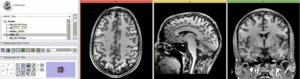

Registration Results

RegLib C15 registered.gif MRI and PET after registration (click to enlarge)